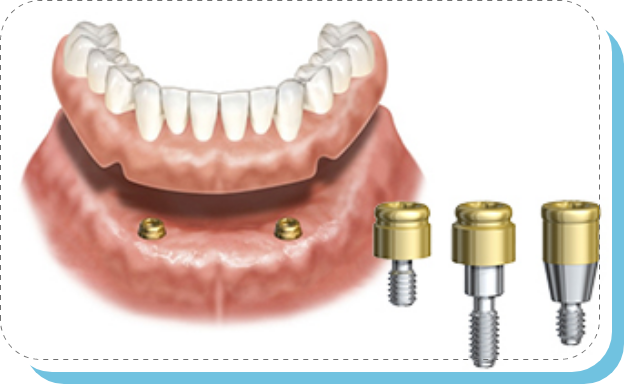

歯を失った部分の顎の骨にインプラントを埋め込み、その上に人工歯、または特殊な入れ歯を装着します。外科手術が必要です。

ノーベル ロケーター アバットメント

ノーベル ロケーター アバットメントとは

ノーベルバイオケア社より発売されたインプラントと入れ歯を結合させ、入れ歯を外れにくくする方法です。

固定式のインプラントを入れ、今お使いの入れ歯にロケーターアバットメントを装着するだけで、 取り外し可能で、外れにくい入れ歯が可能となります。